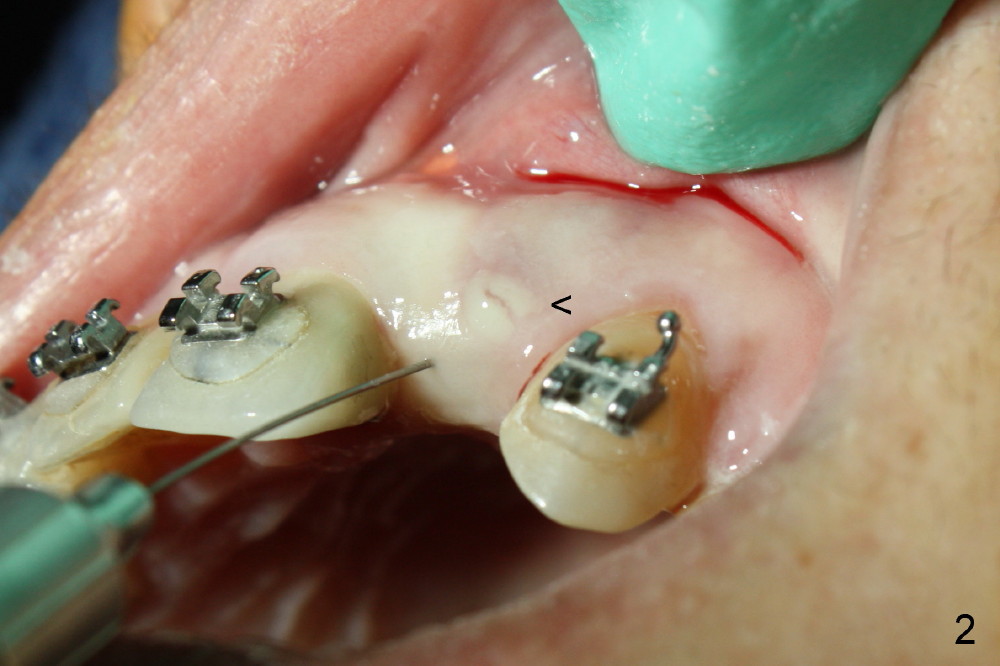

A 56-year-old Oriental lady is going to have immediate implant for the upper left lateral incisor after lengthened preparation (1 2 3 4). There is an indistinct fistula (Fig.1 <) and purulent discharge on anesthetic injection (Fig.2 <). The residual root is exposed (Fig.3 *) following a trapezoidal incision (arrowheads). After tooth extraction and socket debridement with a serrated curette (Fig.4), copious irrigation is conducted with a large monojet and normal saline (Fig.5). The socket will be soaked with non-woven gauze saturated with Clindamycin (Fig.6). The advantage of this antibiotic over Amoxicillin is that there is less mess with the former (completely dissolves). But Clindamycin is bitter. This amalgam well is saved to keep autogenous bone from the reamer and mix with allograft if needed.